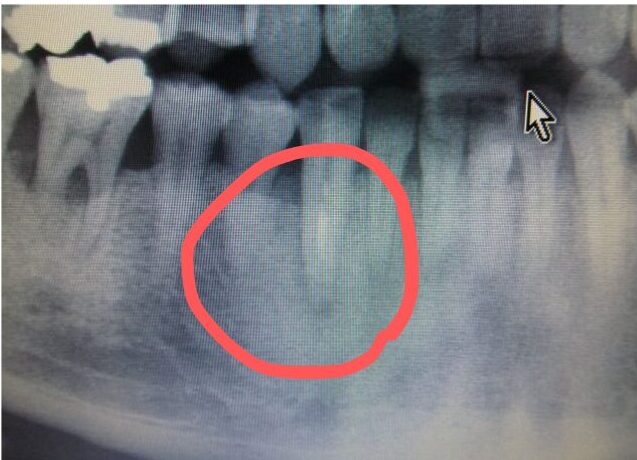

■治療後の変化

7ヶ月後の様子

黒い部分が少し薄くなってきています。

さらに1年後の様子

まだ完全という訳ではありませんが、もうだめだと諦めてしまっている歯でもうまく治療を組み合わせることで残すことが出来ます。